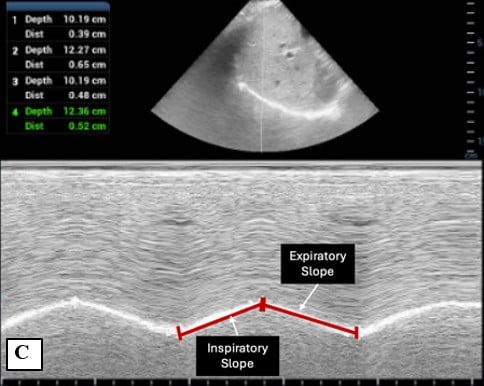

C) Inspiratory and expiratory slope

Inspiratory and expiratory slopes quantify the velocity of diaphragmatic contraction and relaxation, respectively. Evaluated in sub-costal view, they are calculated using the total duration of the respiratory cycle on M-mode. [Table 1] [Figure 1C] While IS and ES have been studied in pediatric respiratory illnesses and show correlation with disease severity, normal reference values for healthy children have not yet been established.3-5